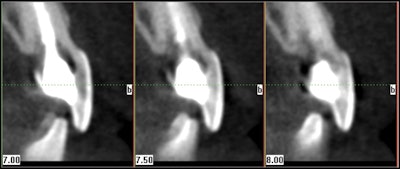

With the different cone-beam CT machines and fields-of -view available, dentists can determine which machine is most appropriate for their practice. A cone beam system with a small field-of-view is especially helpful when viewing one to three teeth maximum. The quality of the images with this machine is beneficial in diagnosing single problematic areas, particularly in resorption defects, fractures, and retreatment cases.

An advantage to large fields of view would be to determine symmetry. Occasionally there will be a lesion present and the need for a scan on the opposite arch is helpful in determining if it is normal. Also when there are difficult teeth to treat, a full scan of one arch can be helpful in determining whether extra canals are truly evident. For example, a retreatment case that is difficult to determine if a 2nd, 3rd, or 4th canal is present due to the prior treatment can also be viewed with its counterpart. If a canal is demonstrated in its counterpart, there will surely be one in the case in question.